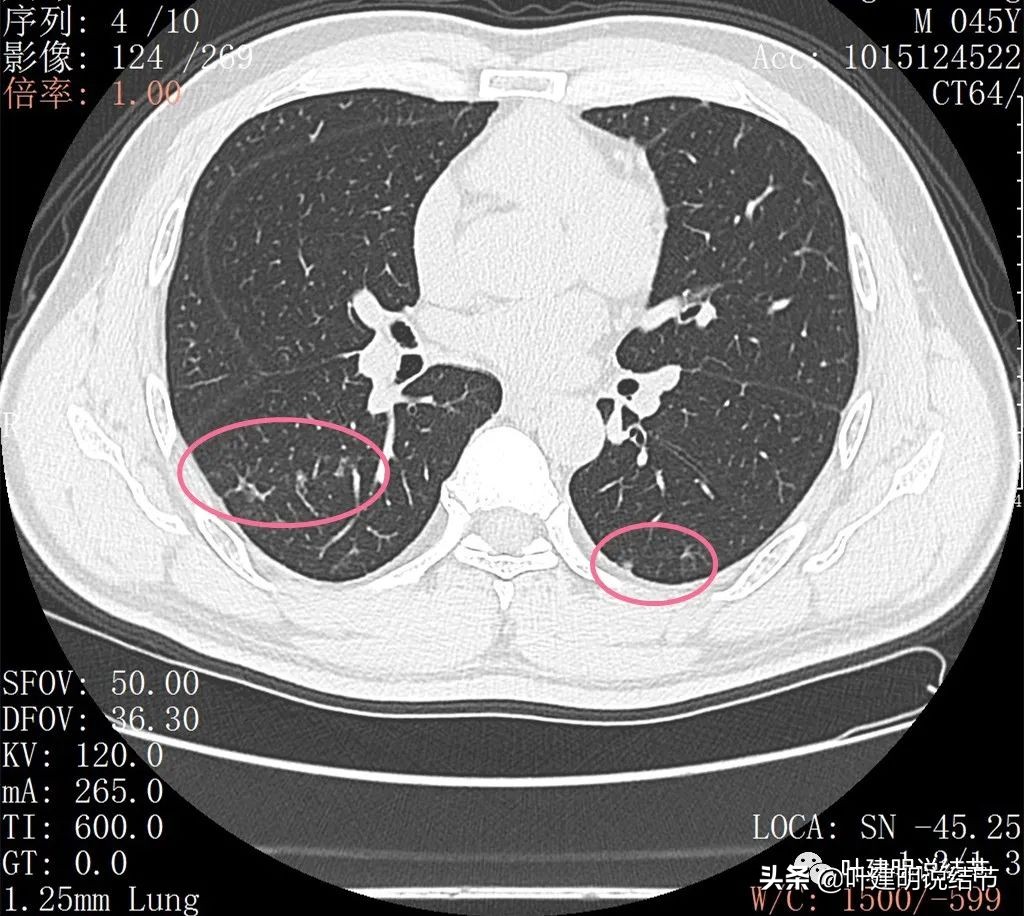

丽水的某A,今年45岁,男性。几个月前检查发现右肺下叶磨玻璃病灶,在当地医院检出后,某市医院胸外科专家看过后考虑恶性可能性大,建议其手术。但他听朋友介绍于2022年2月份来我门诊就诊,予以查了胸部CT平扫加右下叶靶扫描。我们先来看他当时的影像:

2022年2月平扫:

右下叶淡而散在的磨玻璃影

整体轮廓有点清楚,似见血管走行于病灶处

密度略不均